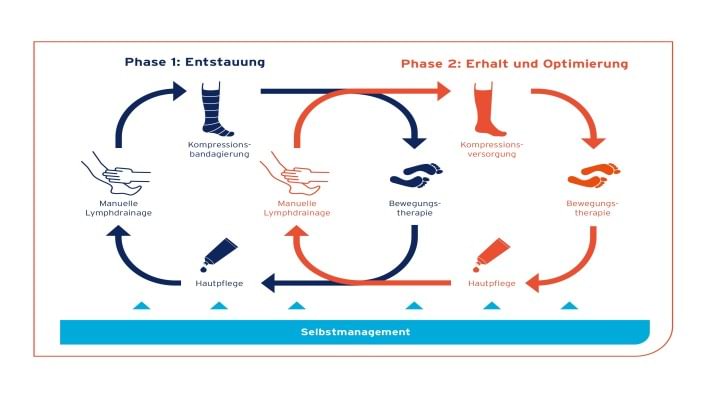

Die Erkrankung des Lymphsystems muss regelmäßig behandelt werden. Geeignet dafür ist die Komplexe Physikalische Entstauungstherapie (KPE).

Je früher Sie mit der Therapie beginnen, umso besser sind die Chancen, ein Fortschreiten zu verhindern und sogar den Zustand zu verbessern.

Die KPE wird in zwei Phasen unterteilt:

- die Phase der Entstauung (blauer Kreis) und

- die Phase der Konservierung und Optimierung (roter Kreis)

Die KPE ist eine kombinierte Behandlungsform, die sich in beiden Phasen aus vier Elementen zusammensetzt, die Voraussetzung für den bestmöglichen Behandlungserfolg sind:

- Hautpflege

- Manuelle Lymphdrainage

- Kompressionstherapie

- Bewegungstherapie

Hautpflege: Die regelmäßige Pflege zum Schutz der Haut ist unverzichtbar, da sie beim Lymphödem zu Entzündung und Infektionen neigt. Die Hautpflege sollte zweimal täglich, morgens und abends durchgeführt werden.

Manuelle Lymphdrainage: Die ML wird von darauf spezialisierten Physiotherapeuten durchgeführt. In der 1. Phase der KPE wird die ML ein- bis zweimal täglich durchgeführt, in der 2. Phase sollte sie dann auf ein- bis dreimal in der Woche reduziert werden.

Kompressionstherapie: In der 1. Phase der KPE erfolgt die Kompressionstherapie mittels Bandagen im direkten Anschluss an die ML.

In der 2. Phase der KPE erfolgt die Kompressionstherapie durch medizinische Kompressionsstrümpfe. Zur Behandlung von Lymphödemen dürfen in der Regel nur flachgestrickte Kompressionsstrümpfe nach Maß eingesetzt werden.

Bewegungstherapie: Sport ist wichtig und sinnvoll – allerdings ist hier ein vernünftiges Maß gefragt. Radfahren, leichtes Lauftraining, Schwimmen und Gymnastik zählen zu den am besten geeigneten Sportarten.